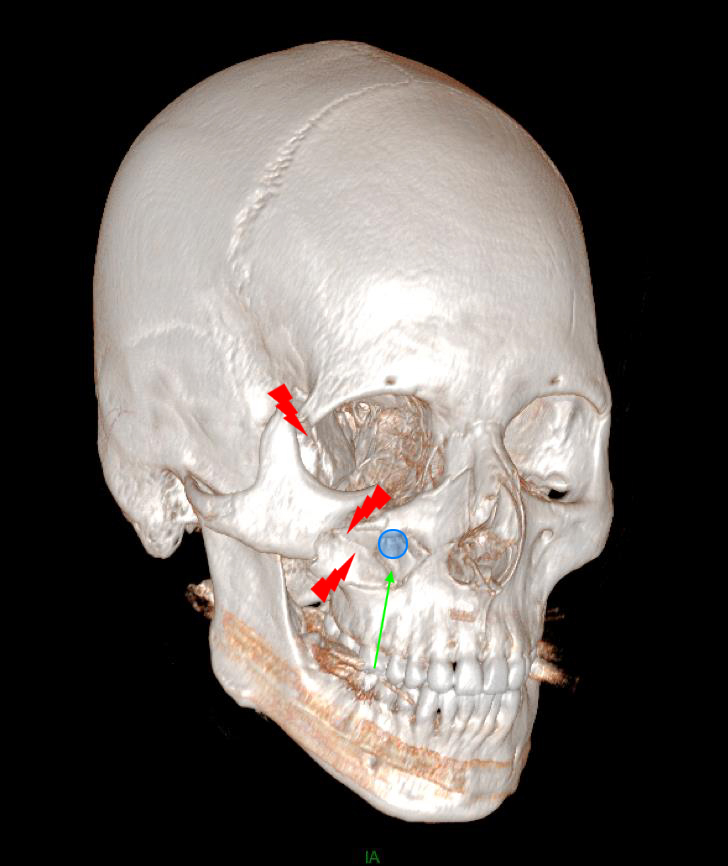

De garde, vous êtes appelé en salle de surveillance post-interventionnelle (SSPI) dans votre hôpital où vient d'être admis un patient conduit sur place par le service d'aide médicale d'urgence (Samu). Il s’agit d’un jeune homme de 20 ans, Monsieur D. Il aurait été victime, entre autres, d’un tir de Flash-Ball lors d’une rixe. Le projectile l’a atteint au niveau de la pommette et de l’orbite droites. Il présente une plaie de la région jugale haute, un œdème des paupières supérieure et inférieure. Vous ne visualisez pas le globe oculaire spontanément. Il est hémodynamiquement stable.

Traumatisme orbitaire = à risque de fracture des parois de l’orbite et donc d’incarcération d’un muscle oculomoteur.